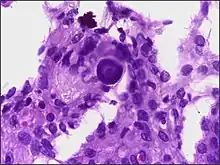

Histopathology of a typical WHO grade 1 meningioma, H&E stain. It is of the meningothelial histologic type, which is the most common meningioma type. It shows its typical findings:

- A woven architectural pattern

- Psammoma bodies (spheroid calcifications)

- Syncytial cells (having indistinct cell membranes) with eosinophilic (pink) cytoplasms

- Round uniform nuclei

- Whorls (concentric cell arrangements)[15]

Histologically, meningioma cells are relatively uniform, with a tendency to encircle one another, forming whorls and psammoma bodies (laminated calcific concretions).[18] As such, they also have a tendency to calcify and are highly vascularized.